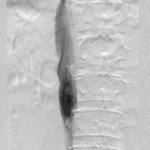

- Inferior vena cavagram before filter retrieval: The axes of the filter and IVC are concordant.